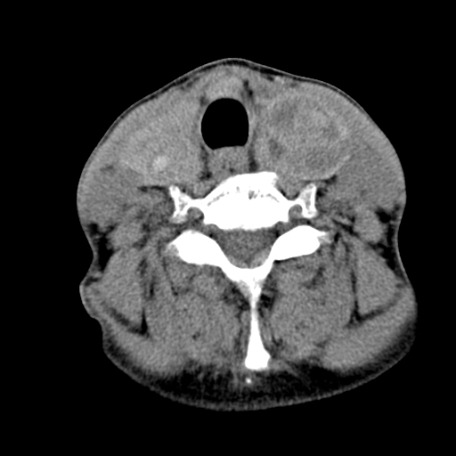

标题: CT24010:患者女56岁双侧甲状腺摘除术后一月复查,患者现感 [打印本页]

标题: CT24010:患者女56岁双侧甲状腺摘除术后一月复查,患者现感

甲状腺术后复发,现在甲状腺区域仍有密度不均匀之软组织密度影。

甲状腺区域密度不均匀密度影,应该是术后改变,要鉴别是否复发,建议增强检查。

“甲状腺摘除术后一月复查”,有病理吗?考虑术后复发,可能是恶性,颌下及左侧颈部淋巴结有肿大。

考虑术后复发,并颈部淋巴结肿大。请结合临床。

双侧甲状腺肿大,周围结构不清,术后复发时间有点短,考虑出血并感染。